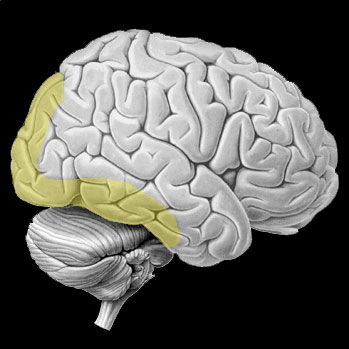

Territoire de l’artère cérébrale postérieure